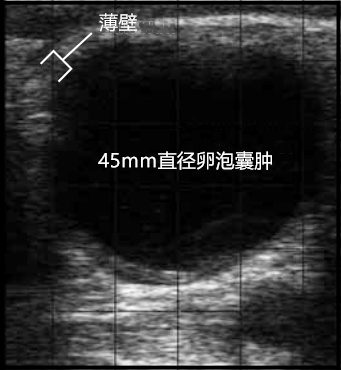

母牛卵巢囊肿的牛用b超图像分析_黄体_液体_薄壁

牛卵泡囊肿b超图超声经济学超声波对牛生殖管理计划的经济价值取决于